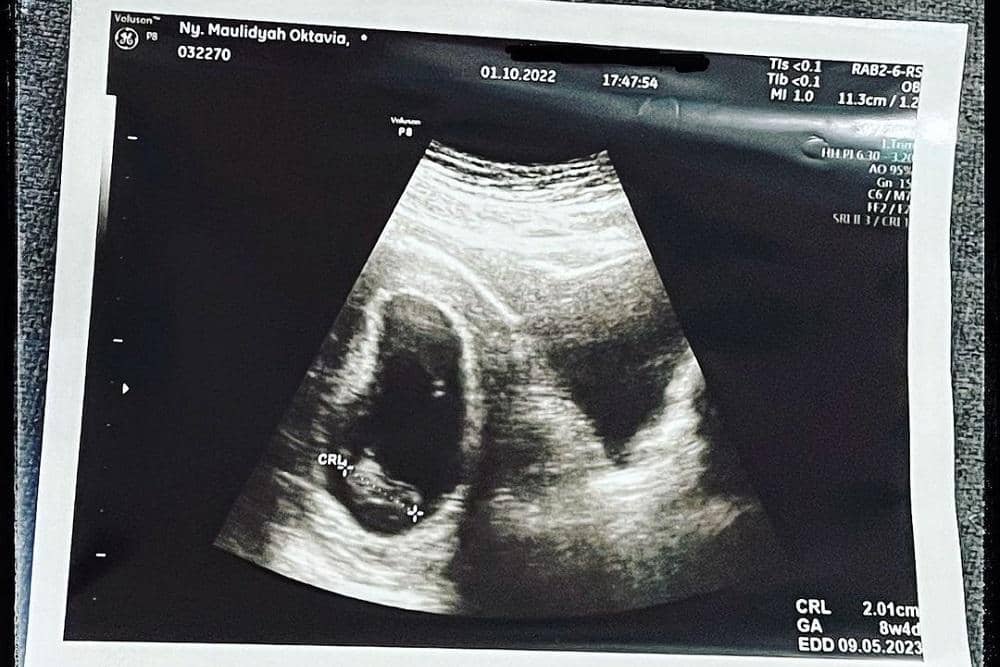

Saat janin dalam kandungannya memasuki usia 8 minggu, Via Vallen dan sang suami, Chevra Yolandi, mendapatkan kabar yang kurang mengenakan. Pasalnya, di usia tersebut seharusnya detak jantung dan gerak janin dalam kandungan sudah bisa terdeteksi melalui USG. Namun, itu tidak terjadi pada calon buah hati pasangan artis itu.

“Di usiamu yang ke-8 minggu, yang seharusnya detak dan gerakmu sudah bisa dideteksi melalui USG, ini malah sunyi, hanya ada bentukmu tanpa adanya suara apa pun,” tulis Via Vallen dalam keterangan unggahannya.

“Menurut hitungan dokter, seharusnya usia kamu 12 minggu, nak. Tapi, hasil USG menyatakan usia kamu masih 8 minggu (sama dengan hasil usg 1 oktober kemarin). Kata dokter, kamu udah nggak berkembang selama 1 bulan. Ami bingung nak, demi Allah bingung. Melihat kondisi yang sekarang, apakah mungkin dengan menunggu lagi, masih ada harapan untuk kamu berkembang dan bisa benar-benar Ami miliki,” sambungnya.